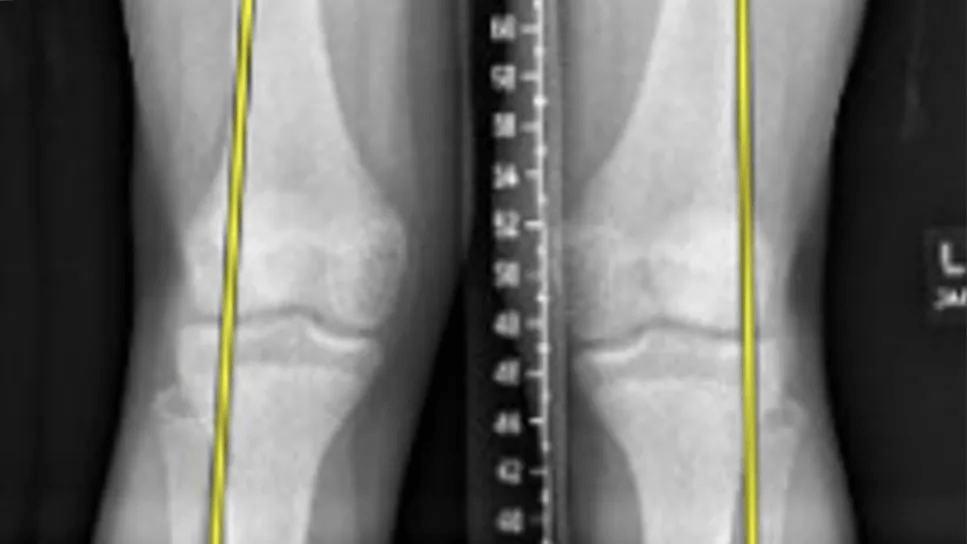

X-ray of patient with knock knees

Genu valgum is diagnosed based on standing full-length radiographs of the bilateral lower extremities. The mechanical axis is drawn from the center of the femoral head to the center of the tibiotalar joint. Genu valgum is diagnosed when the mechanical axis falls lateral to the center of the knee.

The magnitude of the deformity can be assessed by tibiofemoral angle (the angle of the anatomical axes of the femur and tibia) as well as intermalleolar distance (the distance between the medial malleoli when medial femoral condyles are touching).

The mechanical lateral distal femoral angle (mLDFA) and medial proximal tibial angle (MPTA) — the angles formed by the mechanical axes and articular surfaces of the femur and tibia, respectively — can help assess an underlying femoral or tibial cause of the deformity.

A 14-year-old male presented with complaints of progression of genu valgum, with his left knee more pronounced than his right. The mechanical axes passed through the lateral knee bilaterally.

X-ray of patient with genu valgum

X-ray with measurements of patient with genu valgum

Measurements were as follows:

Tibiofemoral angle

Left

15 degrees

Right

13 degrees

mLDFA

82 degrees

84 degrees

MPTA

89 degrees